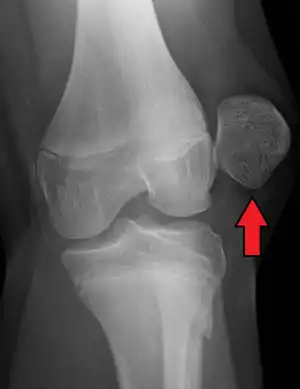

![]() | |

| X-ray showing a patellar dislocation, with the patella out to the side. | |

A patellar dislocation typically occurs when the knee is straight and the lower leg is bent outwards when twisting.[1][2] Occasionally it occurs when the knee is bent and the patella is hit.[1] Commonly associated sports include soccer, gymnastics, and ice hockey.[2] Dislocations nearly always occur away from the midline.[2] Diagnosis is typically based on symptoms and supported by X-rays.[2]